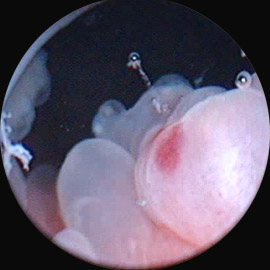

2. Полипоидный/буллезный/папиллярный цистит. Лечение медикаментозное, в некоторых случаях более эффективна лазерная абляция слизистой мочевого пузыря.